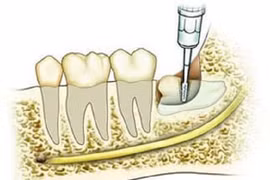

(Kiến Thức) - Nhổ răng là biện pháp nhằm điều trị và khắc phục khi răng khôn mọc lệch. Chế độ dinh dưỡng, cách vệ sinh răng miệng, thể trạng của cơ thể có ảnh hưởng rất lớn tới khả năng hồi phục của vết thương sau khi nhổ răng khôn.